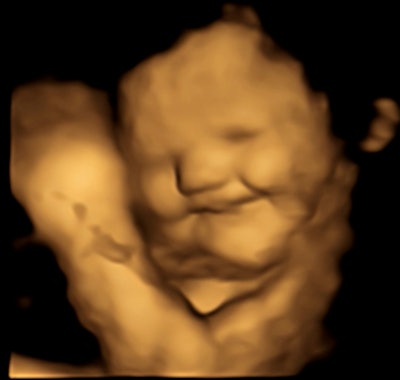

Researchers led by Beyza Ustun from Durham University found via ultrasonic imaging that fetuses gave "cry-face" reactions to kale, which is bitter in taste, and "laughter-face" reactions to sweeter carrot after the mothers ingested capsules for each flavor.

The researchers found that the 35 fetuses exposed to carrot flavor showed "lip-corner puller" and "laughter face" expressions more frequently. Meanwhile, the 34 fetuses exposed to kale flavor showed more "upper-lip raiser," "lower-lip depressor," "lip stretch," "lip presser," and "cry-face" expressions.

Ustun said this effect occurs within a "relatively short" time. Around 30 minutes after the mothers ingested the flavor capsules, ultrasound images showed facial reactions by the fetuses. The flavor content of the capsules undergo digestion, absorption into the mothers' bloodstream, metabolization, and circulation through the placenta and fetus. This results in collection in the amniotic fluid and fetal chemoreception.